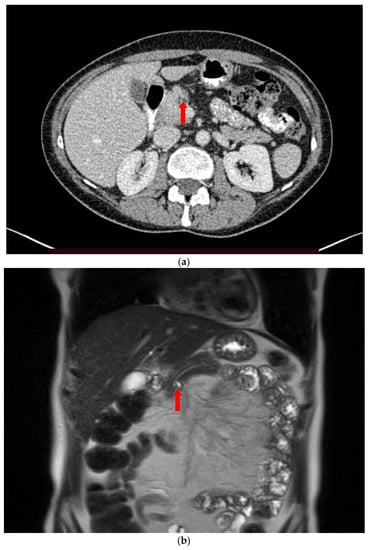

2. Imaging Findings